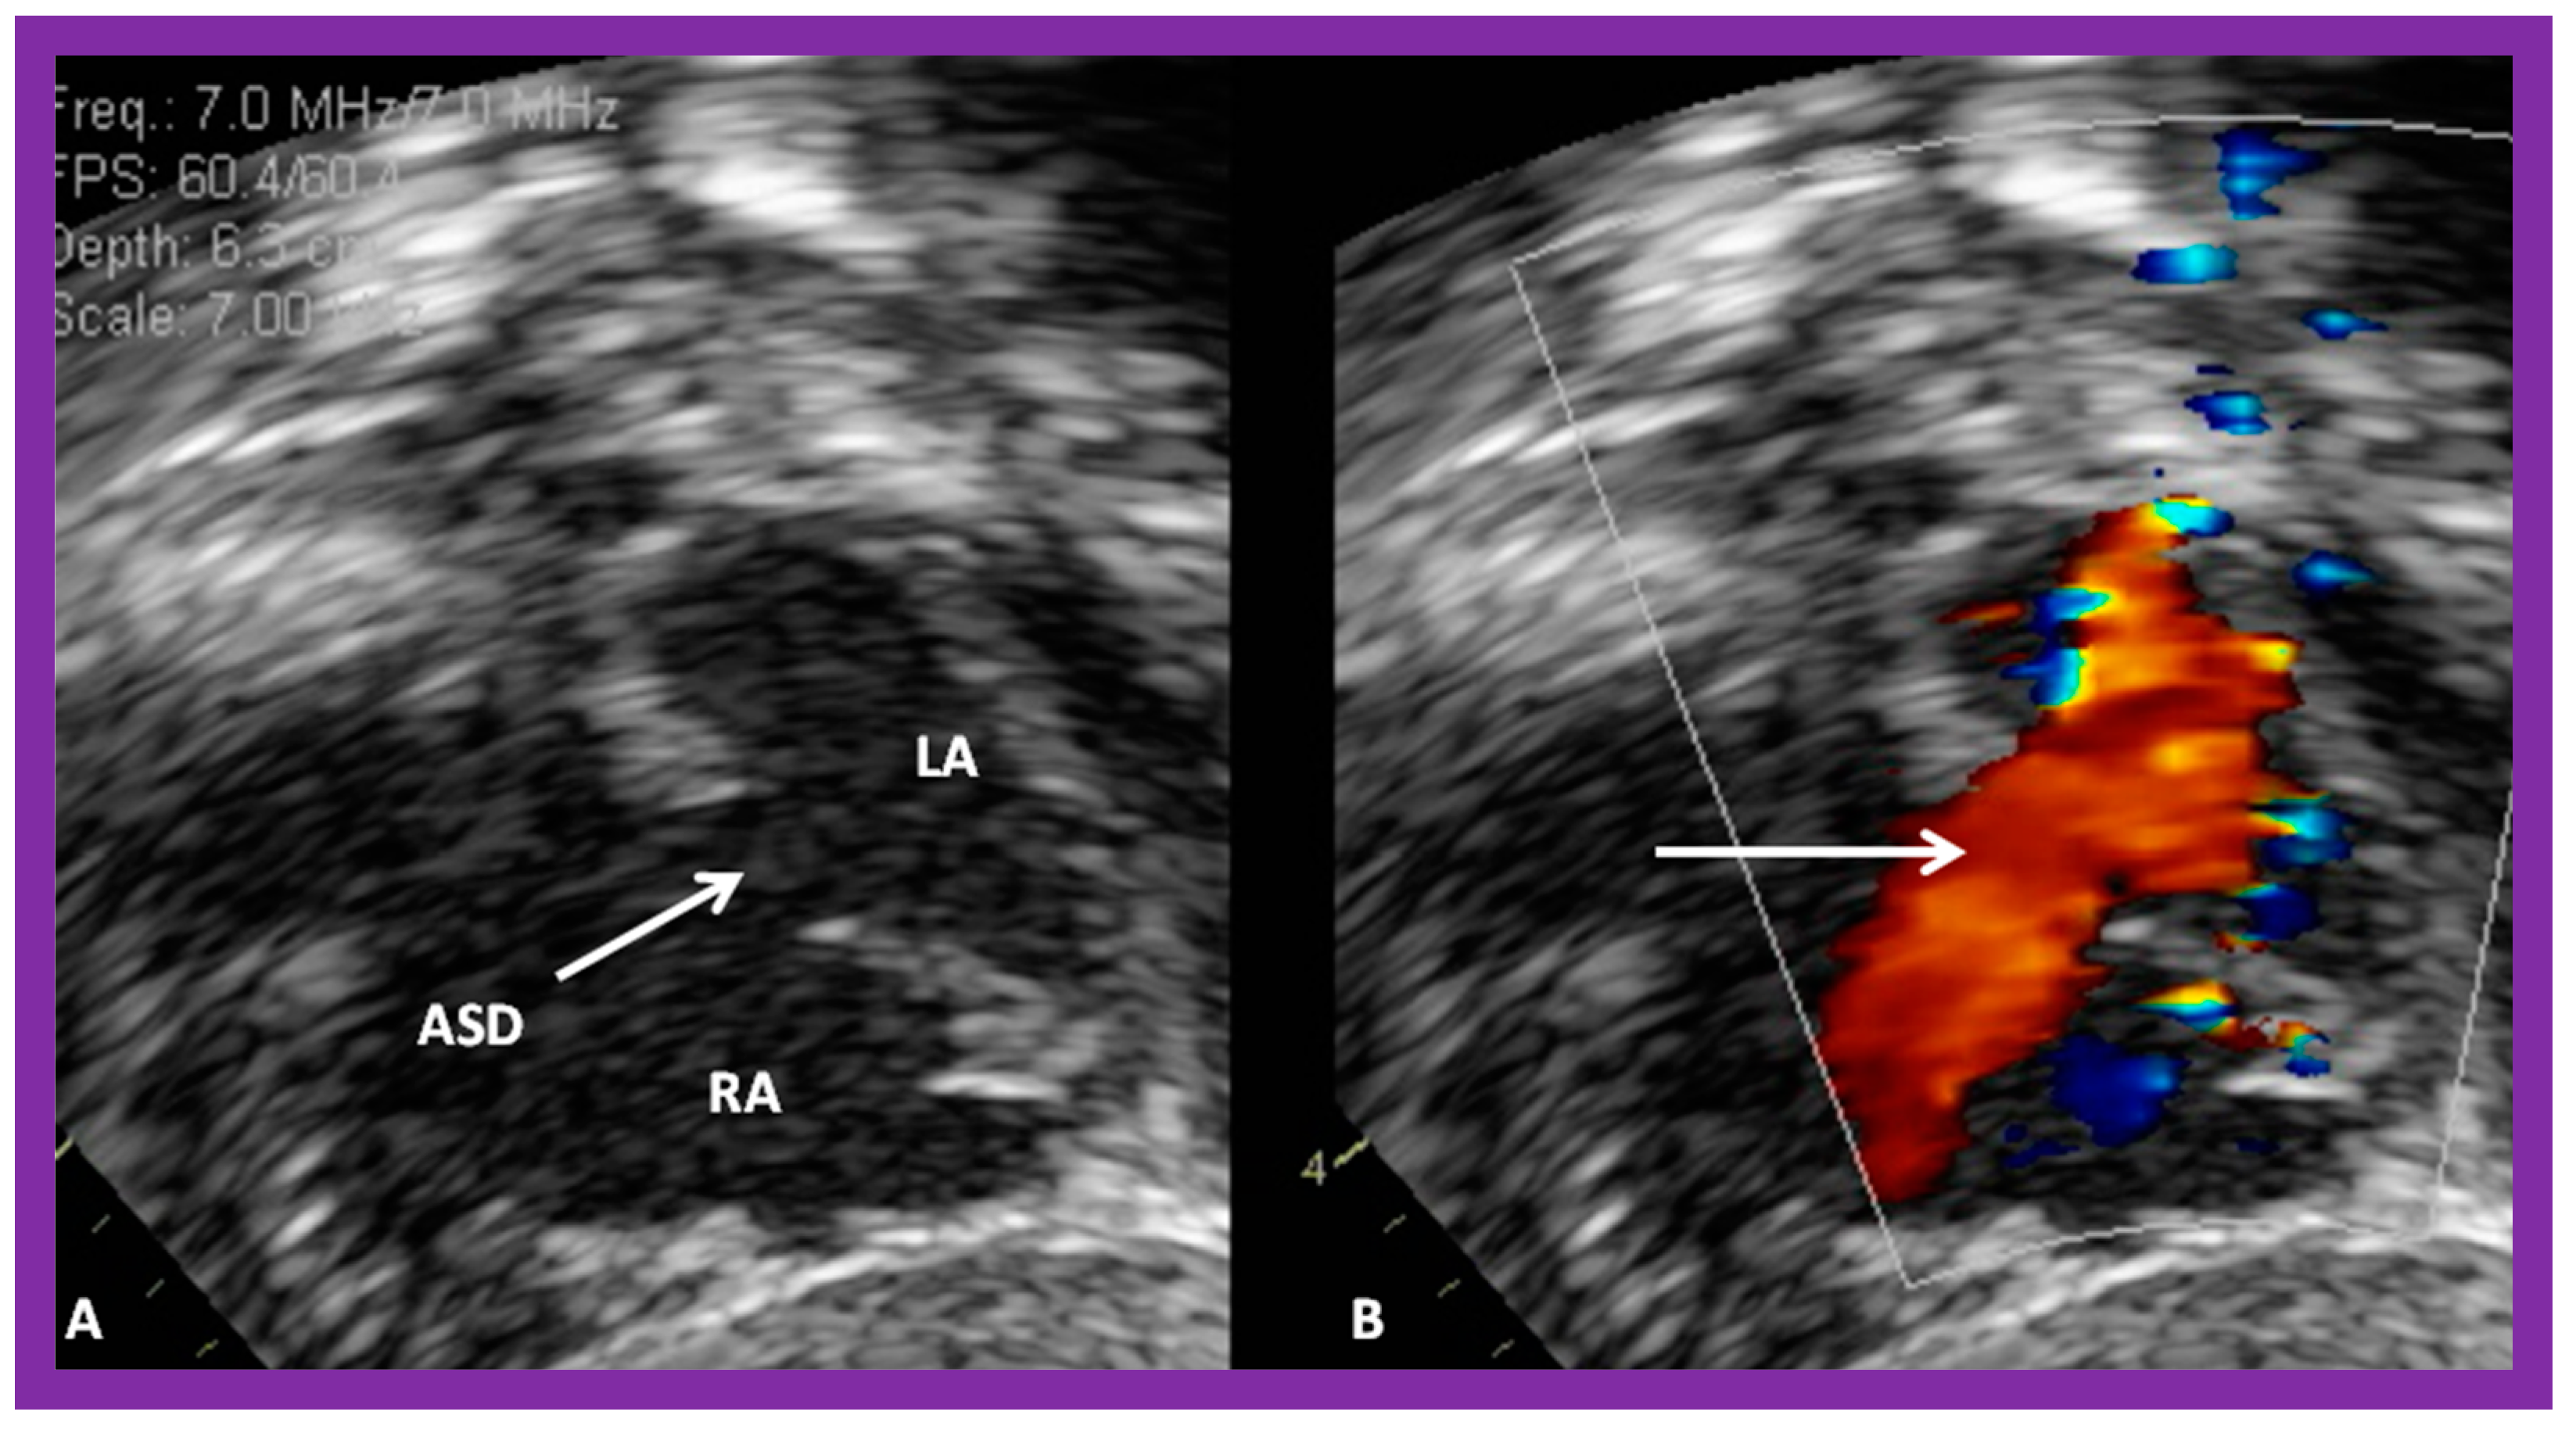

2. Diagnosis